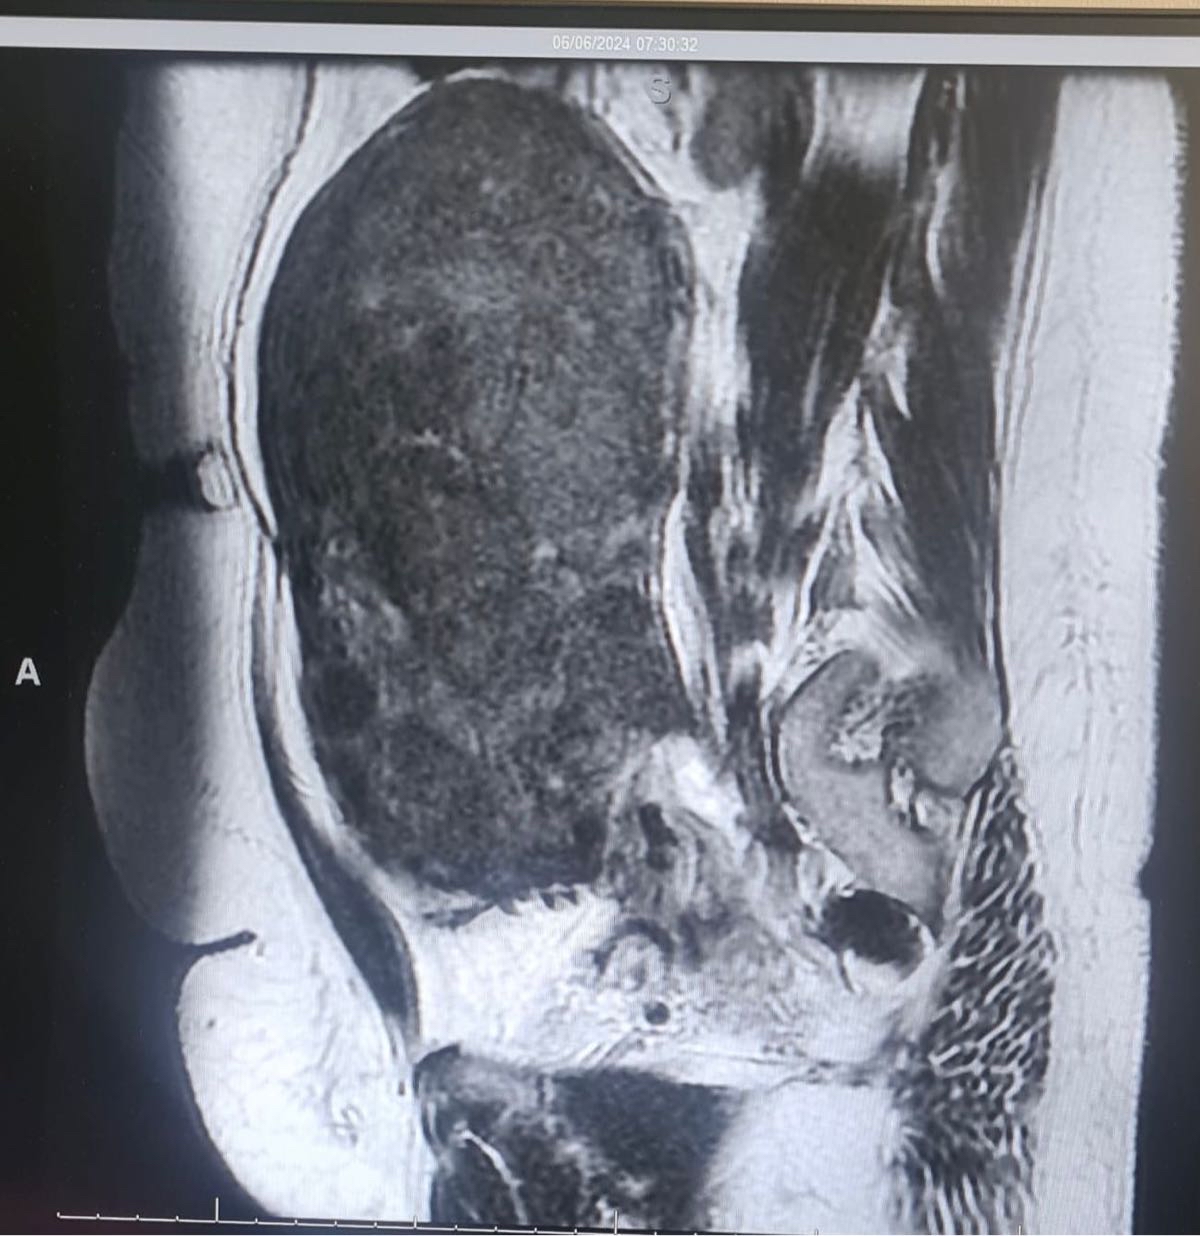

وكانت السيدة تعاني من آلام شديدة وانتفاخ في البطن، مصحوبة بنزيف مستمر استدعى نقل الدم إليها عدة مرات. وبعد إجراء الفحوصات اللازمة، كشفت الأشعة الصوتية والرنين المغناطيسي عن وجود عدة أورام ليفية حميدة تملأ تجويف البطن، أكبرها يتجاوز حجمه 20 سنتيمترًا.